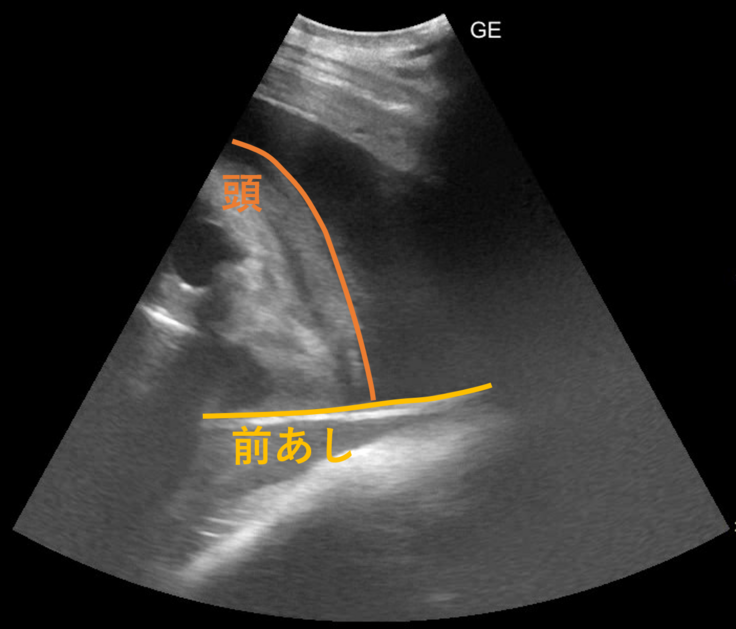

これだと何が映っているのかよくわからないので、線を引いてみました。

最初の画像と見比べていただくと、何となく見えてくるでしょうか。メイのお腹の中の子ゾウの前肢と頭です。目に見える黒い部分が、目なのか、鼻の奥を捉えることができたのかははっきりせず、今後の検査で姿勢があえば追っていく予定です。

クラウドファンディングページで紹介した2024年9月の画像では、胸からお腹にかけてを1つの視野で観察できていました。約半年がたち、検査機器で見ることができる25㎝程度の深さでは、たまたま近くに来ている頭の一部や前あしの一部が観察できる、というところまで成長しています。